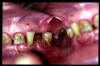

CM Desgaste por bruxismo, presencia de cálculo